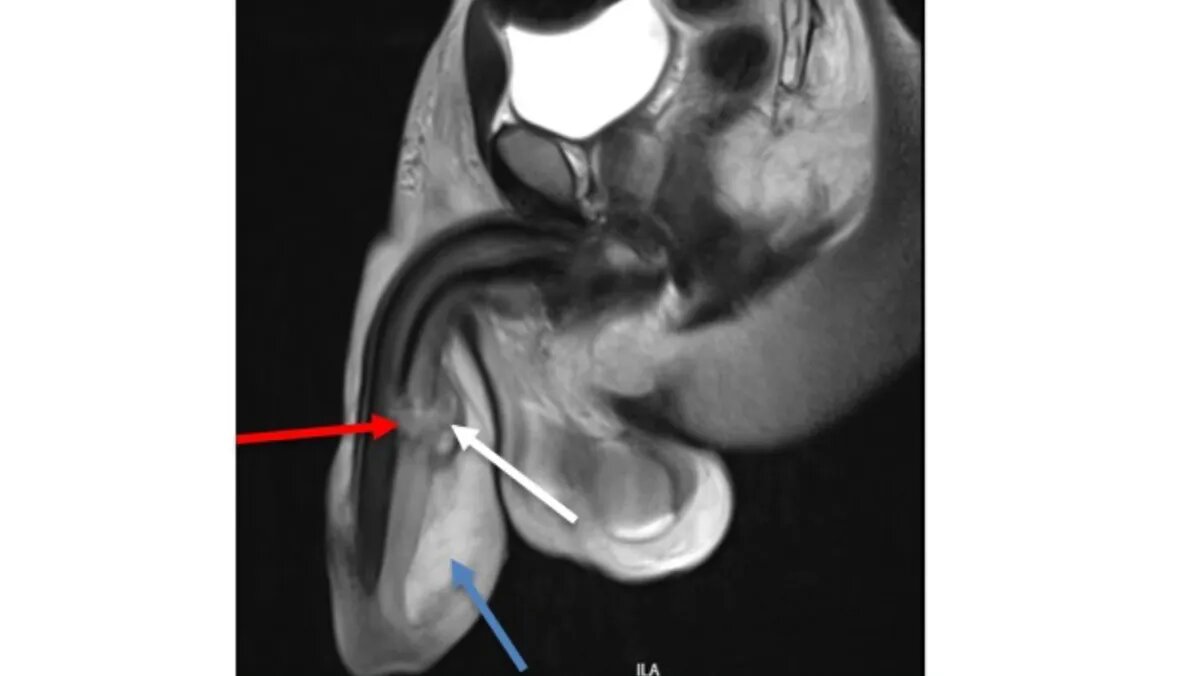

36-летний пациент обратился к врачу с опухшим половым органом и обильным кровотечением из уретры — было принято решение об неотложном хирургическом вмешании. 36-летний житель Танзании обратился в больницу и рассказал врачам, что во время секса со своей партнершей он услышал неожиданный хруст, когда его половой орган случайно выскользнул и ударился о промежность женщины. Звук сопроводился потерей эрекции, резкой болью и кровотечением из уретры. Изначально мужчине дали сильное обезболивающее и направили в другую клинику, чтобы там провели более профессиональное обследование. Вскоре обследование специалистами показало, что мужчина получил тройной перелом полового члена и повреждение уретрального канала — такой случай считается крайне редким в урологических записях и считается опасным. УЗИ показало, что у пациента поврежден кровеносный сосуд и было принято экстренное решение провести сложную хирургическую операцию. Шесть месяцев после операции мужчине потребовалось для прохождения реабилит

Фото: sciencedirect